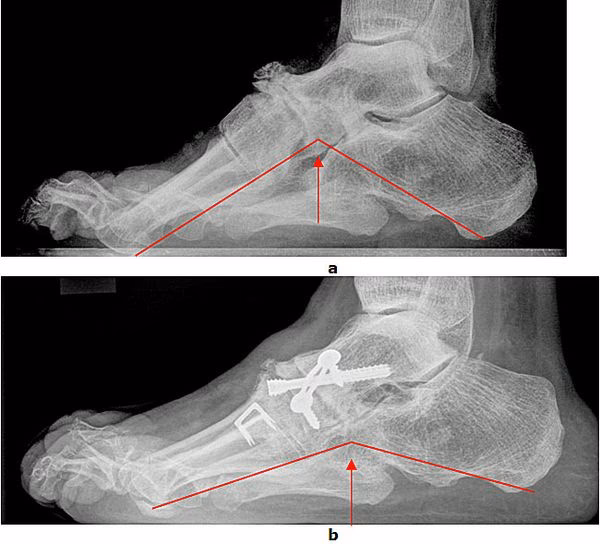

- Knoglekirurgi (Osteotomi): Her korrigeres fodens form ved at gennemskære og genplacere knogler. En almindelig procedure er at ændre hælbenets position for at rette op på fodens akse.